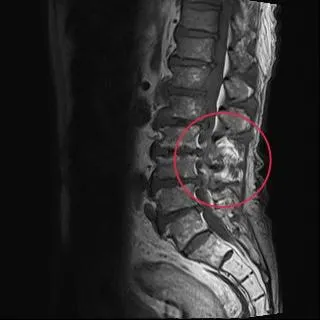

下背痛

感染科

鏈球菌感染

骨髓炎

運動習慣

電腦斷層

止痛藥

脊椎骨髓炎